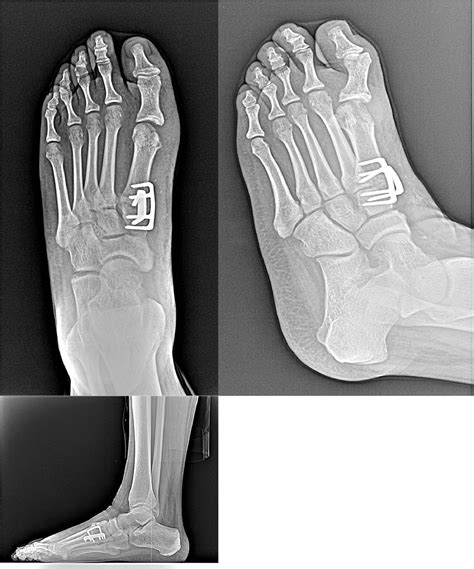

Ankle Fusion Procedures work by removing the damaged cartilage from the joint surfaces of the talus (the top bone of the foot) and the tibia (the shin bone). Once the cartilage is removed, the surgeon uses metal hardware, such as plates, screws, or rods, to hold these two bones together in a fixed position. Over the course of several months, the body naturally heals by bridging these bones with new bone tissue, creating a single, solid bone structure. The primary goal is to eliminate pain by preventing the grinding of bone-on-bone that occurs in advanced arthritis.

• Bone Healing: X-rays will be taken periodically to monitor the progress of the fusion. Weight-bearing is only permitted once there is radiographic evidence that the bones have securely fused.